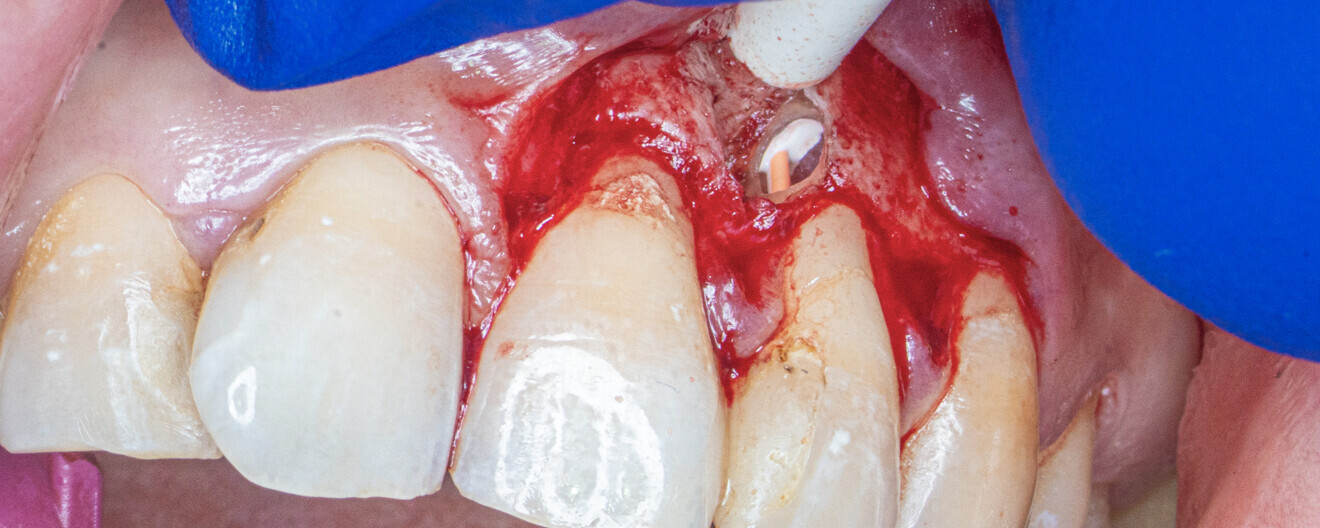

A 40-year-old female patient was referred to the endodontic office because of an incidental finding of IRR in the maxillary left lateral incisor on a panoramic radiograph. A CBCT scan was taken to assess the extent of the resorption, devise a treatment plan and determine the prognosis (Figs. 1a–c). The resorption cavity was located in the middle of the root and had perforated the mesial wall of the root. The rather round and regular shape of the resorption indicated the inflammatory type. The osteolytic focus suggested a lesion was present next to the perforation area (Fig. 2). Owing to the size of the wall perforation and the presence of the lesion, the treatment plan involved a single-session root canal treatment as well as a surgical approach.

After performing local anaesthesia, the access cavity was created. The pulp chamber was reshaped with an ultrasonic diamond-coated tip. The pulp chamber was cleaned with sodium hypochlorite, and the pulp tissue was partially removed from the root canal. An incision was made from the frenulum, through the gingival sulcus from the maxillary first incisor to the maxillary canine. After raising a flap, the granulation tissue was removed from the resorption cavity with a small excavator.

An incision was made from the maxillary left central incisor through the gingival sulcus to the right maxillary canine. After raising a flap, the granulation tissue was removed from the resorption cavity with a small excavator (Figs. 9–11). The root canal shaping protocol was performed with conventional chemomechanical preparation. The shaping sequence began with negotiation with passive hand files, followed by preparation with rotary files and irrigation using sodium hypochlorite with manual needle agitation. The irrigation protocol was performed as described in Case 1.